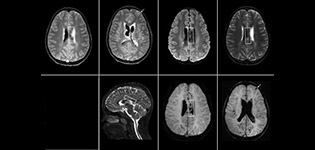

SWIp supports diagnostic confidence in traumatic brain injury

The value of susceptibility weighted imaging in visualizing brain injury is well documented. The Philips multi-echo SWIp technique provides fast susceptibility weighted imaging with enhanced susceptibility contrast and high resolution.

“Pediatric imaging is not without its challenges,” Dr. Miller says. “Since our patients are often very small, we need very high-resolution imaging. In cases of brain injury, we need to obtain information quickly so the treating clinicians can make decisions on care. We rely on high resolution and robust imaging capabilities, and SWIp provides that.”

“SWIp helps us identify blood or blood products, calcification, and diseases that affect the vascular system,” says Dr. Miller. “In children with traumatic brain injuries, it highlights areas that are injured, better than some of the previous techniques that we were using. These children often have micro-injuries that cause small amounts of blood or tissue damage. Adding SWIp helps us to better characterize the extent and nature of the injury. Having characterized an injury to the extent of what’s possible supports our diagnostic confidence.”

Full adoption after initial comparison

“I would definitely recommend other users to implement SWIp. We initially added the SWIp sequence following a lot of support for its utility in the literature. Then we directly compared SWIp to the 2D gradient echo sequences that we were using. After a good amount of clinical experience in seeing its benefits, we were confident to replace the old sequences with SWIp. It gives us a better assessment of the physiological processes of the brain that were less apparent on our previous imaging sequences,” says Dr. Miller. “SWIp is now a routine sequence for imaging traumatic brain injury patients at PCH, and it’s episodically added for patients who have intracranial vascular abnormalities.”

“I believe SWIp is rapidly becoming the standard in imaging traumatic brain injury, because of its high sensitivity to venous blood products. SWIp may even help attract patients; our neurosurgeons often ask to have the patients imaged on our scanners with highly sensitive techniques like SWIp. There’s also a growing application of SWI sequences in other vascular abnormalities because of the possibilities around physiological assessment of the brain than just a standard structural imaging.”